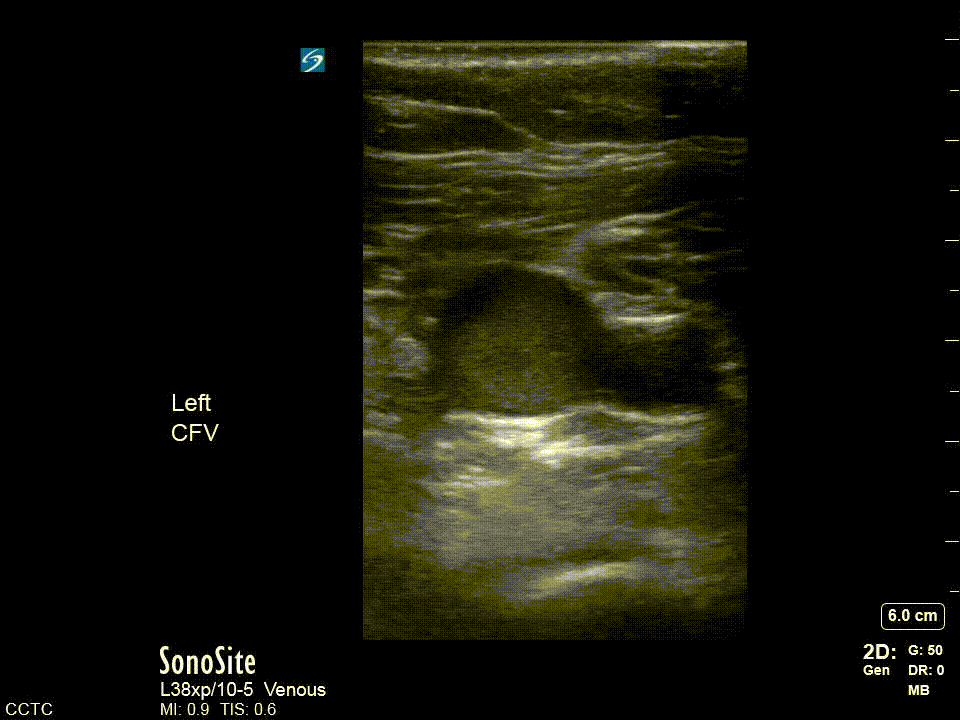

Positive: In this case we are looking at a completely occluded popliteal vein (with no compression applied) and on the immediate right a branch vessel as well. In complete occlusions it might be difficult to discern the vein especially if it is more chronic and more isoechoic with the surrounding tissue. This highlights why it is so important to visualize the artery as it assists with localization.